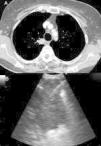

The EUS-B scope is inserted through the mouth into the esophagus gently rotating it with a screw movement, and advanced under visual control to the gastric fundus. While introducing the scope, suction should be used only in an intermittent manner, to avoid deflating the esophageal tract completely. The endoscopic view is not normally useful and endosonography scanning guides the procedure. From this moment on, continuous suction is mandatory to facilitate the contact between the ultrasound transducer and the esophageal wall. At the cardia region, the transducer is turned back until the abdominal aorta is clearly visualized in its longitudinal diameter (Fig. 4). To identify the LAG, the tip of the bronchoscope is slid down the aorta, up to the celiac trunk and mesenteric artery, which are the first vessels extending from the abdominal aorta. At this point, the EUS-B scope is turned counterclockwise (if the physician is standing behind a patient lying in supinal position this movement turns the transducer to the left) to visualize the left kidney, the spleen, and the LAG just behind the celiac trunk and mesenteric artery. After seeing the LAG, the transducer is brought back to its standard neutral position at the cardia. In front, the left lobe of the liver, diaphragm and heart are clearly visualized (Fig. 4A), and to the right the hepatic veins can be followed as they approach the inferior vena cava. Then scanning proceeds by withdrawing the transducer to the distal esophagus. The EUS-B scope is turned around from the descending aorta and back to the aorta again (Fig. 4B), visualizing retroperitoneal and para-aortic lymph nodes. If the scope is turned slightly more to the left, the diaphragm is clearly seen on the left corner and the right atrium on the right. At this level, the left pulmonary ligament lymph nodes (station 9) can be detected. During further withdrawal of the scope, from the distal to the middle part of the esophagus, para-esophageal (station 8) and lower para-aortic lymph nodes are seen posteriorly. Then the heart is visualized anteriorly, with the left ventricle coming first into focus, at that point the atrioventricular valves and the left atrium with pulmonary vein close to the esophageal wall. While withdrawing the scope slightly more, subcarinal lymph nodes (station 7), especially the posterior group, are clearly visible (Fig. 4C), and to the right, reflections from the trachea and the proximal wall of the right main bronchus are seen, as well as the right pulmonary artery in a transverse section. Further retreating the scope and looking anteriorly at the tracheal reflections at its lower part, slightly to the right, the posterior part of the right paratracheal lymph nodes (station 4R), behind azygos vein, can be found in many cases. At this level, rotating the EUS-B scope to the left will permit to detect the lower paratracheal (station 4L) and deeper aorto-pulmonary window lymph nodes (station 5) between the pulmonary artery and aorta (“mickey mouse effect”) (Fig. 4D). On the left, the entire descending intrathoracic aorta can be followed along the esophagus, and para-aortic lymph nodes (station 6) may be visualized through the aortic arch. Behind the aorta, reflections from the thoracic spine are well seen. As the EUS-B scope is further withdrawn, the left subclavian artery and upper left paratracheal lymph nodes (station 2L) are identified on the left side, and just behind them the left internal jugular vein is often found (Fig. 4E). To the level of the upper part of the esophagus, both lobes of the thyroid gland can be seen and below them seldom mediastinal highest lymph nodes (station 1) can be seen.

The technique for needle biopsy aspiration is similar to the one performed for EBUS-TBNA, but often easier because of the softness of the esophageal wall. On the other hand, the EUS-B-NA seems to be more difficult because of incorrect adjustment to the esophageal wall. Therefore, the reach of EUS-B is the same as for EUS: it is possible to puncture the LAG, left lobe of the liver, lymph node stations 2L, 4L, 7, 8, 9 (Fig. 5) and in specific situations the lower part of station 5, posterior part of station 4R and station 1.